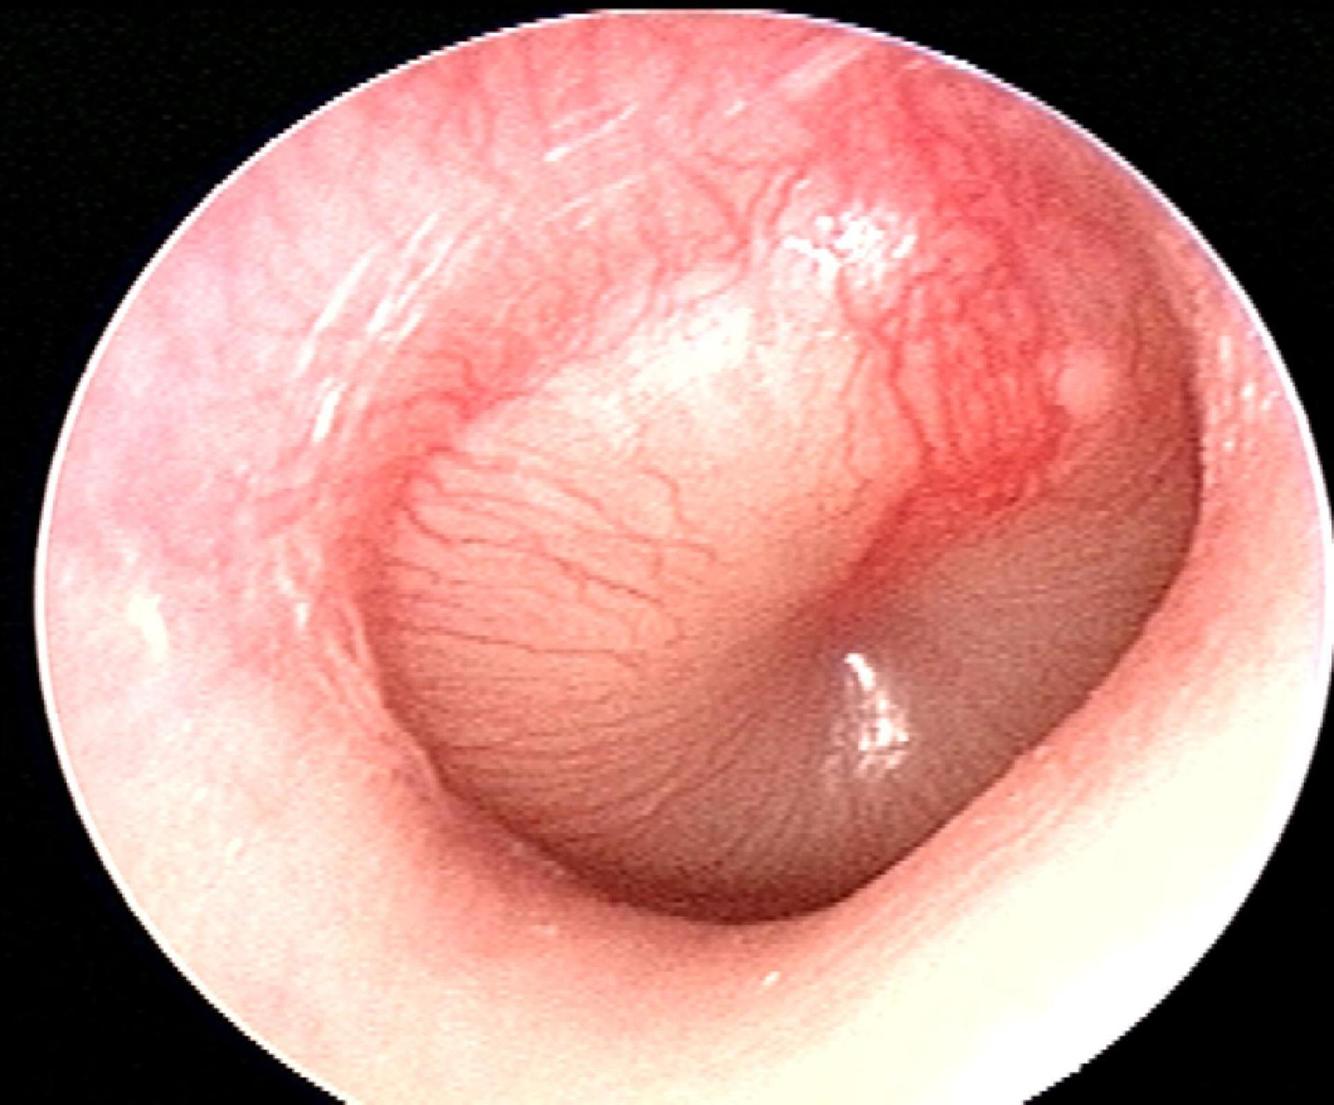

Otitis Media

Otitis Media: Dx & Tx

Name & describe HPI/PE